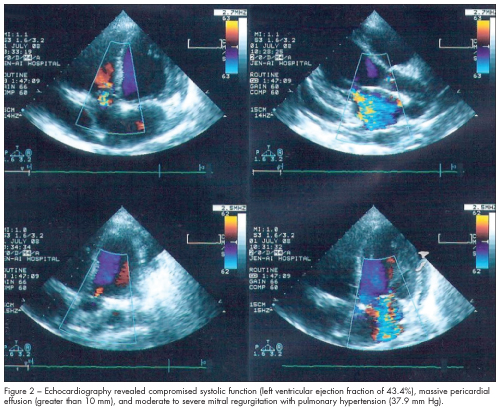

An ECG showed sinus tachycardia, with a heart rate of 130 beats per minute. A chest film taken on admission showed cardiomegaly with pericardial effusion (Figure 1). Echo-cardiography confirmed the cardiomegaly with compromised systolic function (left ventricular ejection fraction of 43.4%), massive pericardial effusion (greater than 10 mm), and moderate to severe mitral regurgitation with pulmonary hypertension (37.9 mm Hg) (Figure 2).

Echocardiography is particularly sensitive and specific in detecting cardiac abnormalities, such as mild pericarditis, valvular lesions, and myocardial dysfunction. It should be performed periodically in patients with SLE.5